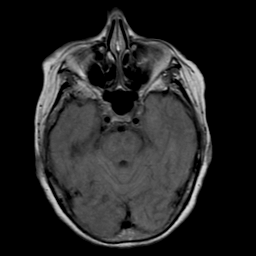

Stroke: proton density-weighted MR #2 -- Slice #7

[Home][Help][Clinical] Slice 7